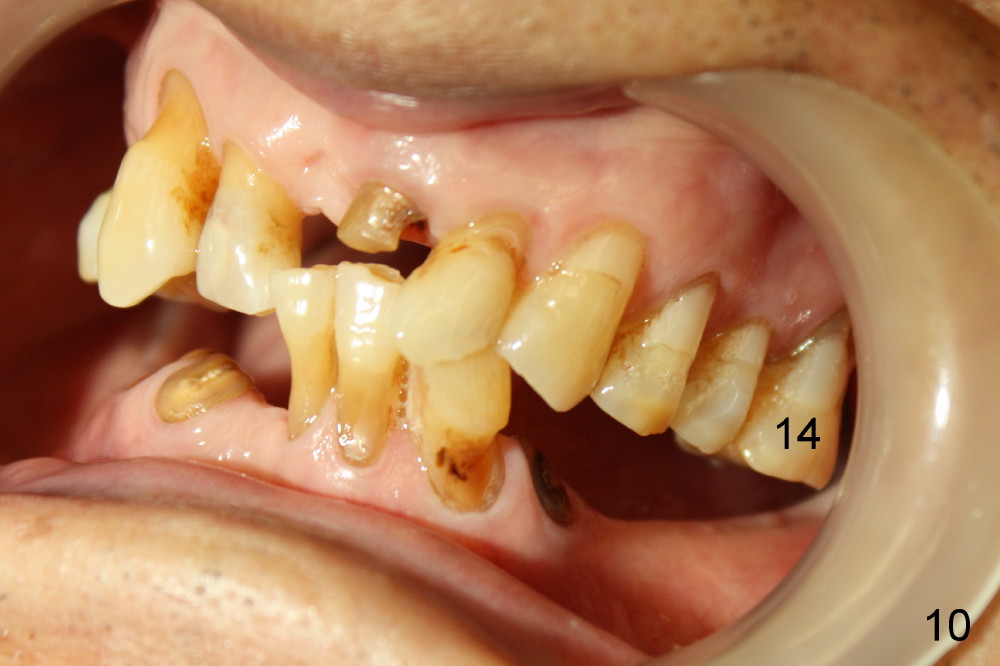

The tooth #14 is periodontally compromised with supraeruption (Fig.8-10). After immediate implant, bone graft (red circles) is needed distally (Fig.8) and palatally (Fig.9).